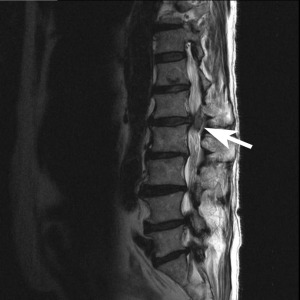

Below are two images, which one looks more painful?

These two images are both “bad” for the patient, but you cannot tell the extensive injuries by simply looking at an image. There is no pain visible in either of them. Letter A is a significant herniation, pressing directly on the spinal canal, and impeding on the spinal cord itself. Letter B, has a piece of vertebral disc that has broken off within the spinal canal (known as a sequestration) and has migrated upwards.

With reference to images A and B above. Image A has cauda equina syndrome, known as complete loss of function of the muscles and structures of the “saddle” area of the pelvis. While Image B is paraplegic from the legs down, without any “saddle” disruption. Both of these cases are no longer considered “conservative” with terms of treating, they are immediate surgical candidates. Disc injuries range from non-painful, to extremely painful, to absolute medical emergencies.